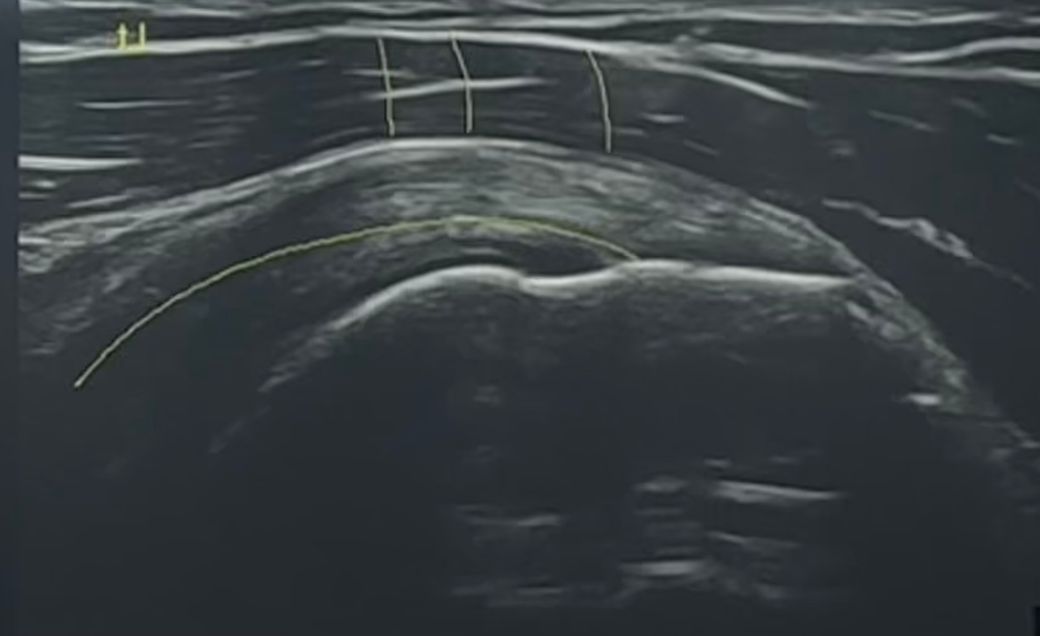

극상근 부분입니다.

초음파사진 촬영한 부분입니다.

• 1번 째 사진

(제 눈에는 1/4인 대략 25퍼센트 정도로 보이는데 그렇게 보면 될까요)

초음파상 극상근의 부분 파열이 25% 내외로 보인다면 비교적 경미한 편이고 운동 시 통증이 없고 기능이 유지된다면 보존적 치료로 충분히 관리 가능합니다.